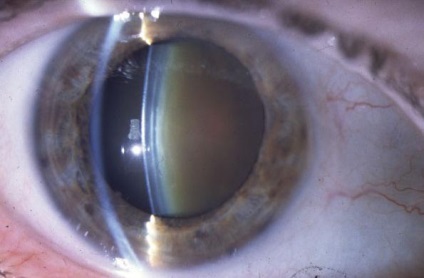

Adesea, există o astfel de patologie, cataracta, sau opacifierea cristalinului. In fata sunt, în funcție de dispunerea zonei de turbiditate, stratificat, forme nucleare, spate și alte ale bolii. Cataracta poate fi congenitală sau dobândită în timpul vieții, ca urmare a traumatismelor, legate de varsta, si o serie de alte motive.

legate de varsta opacități se dezvolta mult timp, până la câțiva ani. Din cauza acestei tulburări de vedere la un ochi pot trece neobservate pentru o lungă perioadă de timp. Dar, chiar și la domiciliu, puteți determina prezența cataractei. Pentru a face acest lucru, trebuie să te uiți la o foaie de hârtie cu unul, apoi celălalt ochi. În prezența bolii ar părea că foaia este plictisitoare și are o tentă gălbuie. Persoanele cu aceasta tulburare au nevoie de o lumină strălucitoare, în care se pot vedea bine.

Opacifierea cristalinului poate fi cauzată de prezența inflamației (iridociclita) sau utilizarea prelungită a medicamentelor, care conțin hormoni steroidieni. Diferite studii au confirmat faptul că, în ochii glaucom opacifierea cristalinului optic este mai rapid.

Diagnosticul constă într-o testare viziune și a structurilor de cercetare a ochiului cu un dispozitiv optic special. Oftalmolog evaluează mărimea și structura a cristalinului determină gradul de transparență sale, prezența și locul de ceață, ceea ce duce la o scădere a acuității vizuale. În cazul în care studiul de lentile sunt metoda de iluminare laterală focală în care suprafața frontală a acestuia inspectate, localizate în interiorul elevului. Dacă nu există nici un nor, obiectivul nu este vizibil. În plus, există și alte metode de investigare - examinare în lumina transmisă, studiul folosind o lampă cu fantă (biomicroscopie).

Tratamentul chirurgical este, în principal. lanturi de farmacii oferă diverse picături, dar acestea nu sunt în măsură să se întoarcă transparența cristalinului, și nu garantează încetarea bolii. Chirurgia este singura procedură care să asigure o recuperare completă. Pentru chirurgia cataractei poate fi utilizată extracția extracapsulară cu suturi pe cornee. Există, de asemenea, o altă metodă - facoemulsificarii cu incizii minime cu auto-etanșare. Metoda de îndepărtare este selectată în funcție de densitatea și opacitatea la starea ligamentelor. Nu mai puțin importantă este experiența medicului.